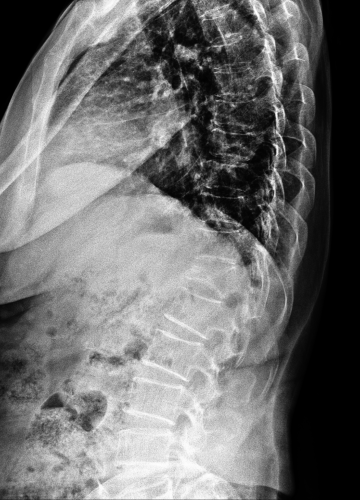

척추골절

척추뼈가 외부 충격으로 인해 찌그러지고 골절되는 질환입니다.

척추뼈의 경우 팔과 다리뼈의 골절과는 다르게 뼈가 찌그러지듯이 납작해지기 때문에 '압박골절'이라 표현합니다. 외형상 변화가 없이 때문에 발생된 후에도 잘 느끼지 못한 채 방치하는 경우가 많습니다.

압박 골절된 척추뼈 (2016.03.18)